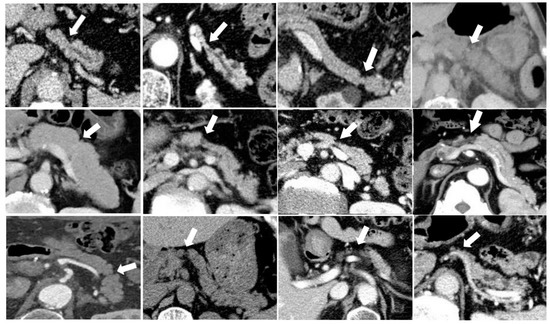

3.5. Case Presentation